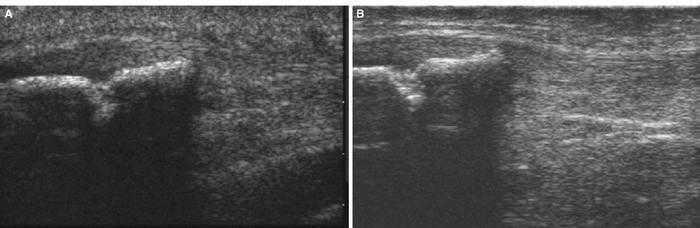

Utilizando el equipo E-A, mediante corte transverso sobre el músculo contusionado se observa (fig. 1A) la imagen de predominio hiperecoico y en su interior la zona oval hipoecoica con mala delimitación de los bordes y con mala definición del contenido, lo que la hace compatible con un lesión muscular por mecanismo extrínseco. La imagen del equipo E-B presenta también un aspecto hiperecoico, si bien la zona oval hipoecoica/anecoica presenta bordes muy bien marcados y se observa con detalle que en el interior existe un contenido heteroecoico que corresponde a las zonas de reabsorción del hematoma (fig. 1B). Todos estos signos permiten el diagnóstico preciso de la lesión muscular extrínseca.

Figura 1 A) En el corte transverso con E-A se observan imágenes hipoecoicas en el vientre del músculo gastronemio interno. B) En el mismo corte, con el equipo E-B se delimita exactamente la zona lesionada del área muscular indemne que lo rodea.

Utilizando el equipo E-A, en un corte longitudinal sobre el músculo gemelo externo a la altura del tercio superior (fig. 2A) se observa la referencia ósea que corresponde a la cortical del peroné, y en un plano superior no se aprecia discontinuidad focal de las fibras ni la presencia de un hematoma intramuscular, debido posiblemente al prolongado tiempo de evolución (1 mes). Por el contrario, con E-B se aprecia una zona hipoecoica en el vientre muscular del gemelo externo (fig. 2B), de aspecto irregular y lineal no visualizable con el E-A, lo cual facilita la confirmación ecográfica de la sospecha clínica.

Figura 2 A) Aspecto fibrilar normal en un corte longitudinal del músculo gastrocnemio externo sobre el peroné en una imagen de E-A. B) En un corte longitudinal con E-B se observa el área hipoecoica en el vientre del gemelo externo.